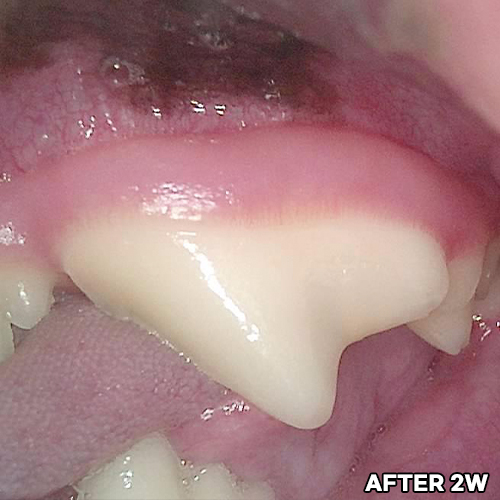

[강아지 치아의 구멍 레진치료 후 2주 경과]